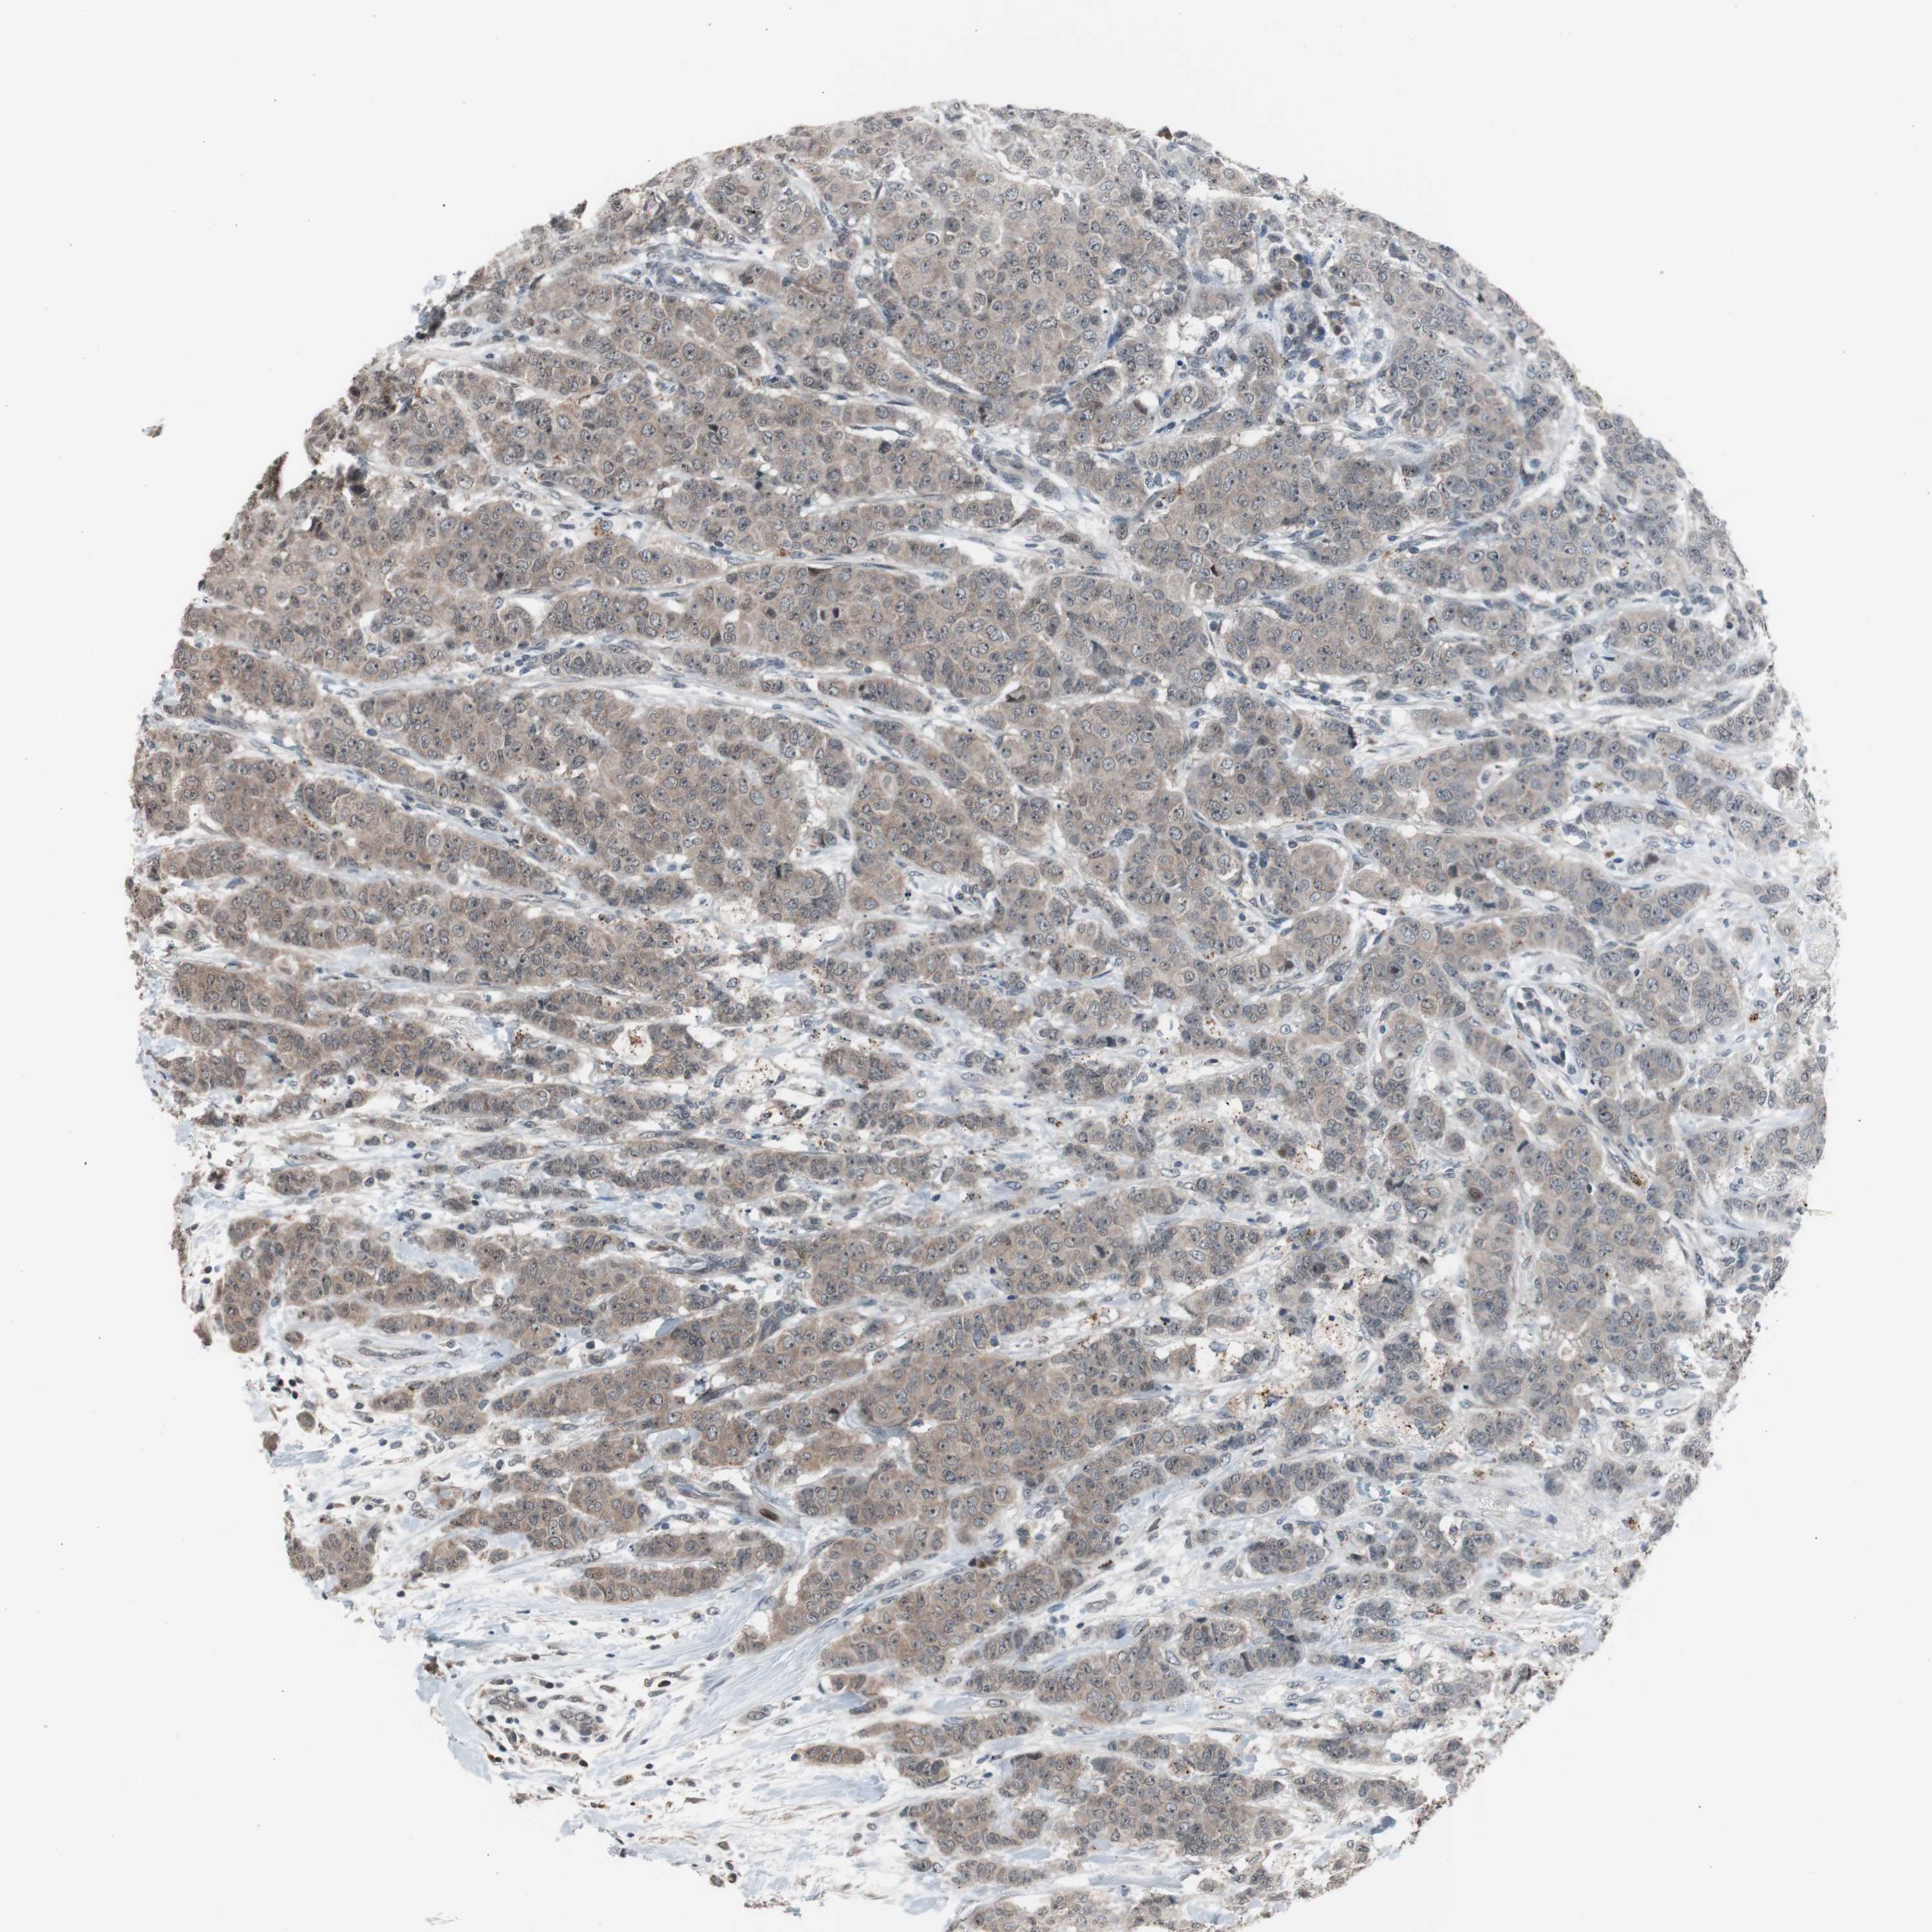

BRCA TCGA BRCA VALIDATION PROTEIN EXPRESSION